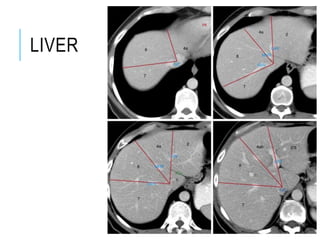

LIVER

Upper margin: level with

xiphisternal joint, 5th intercostal

space 7-8cm from midline; on L,

5th rib on R.

R border: ribs 7-11 in mid-axillary

line.

Lower border partly lies along

right costal margin, crosses in

upper abdominal wall, hands

breadth below xiphisternum